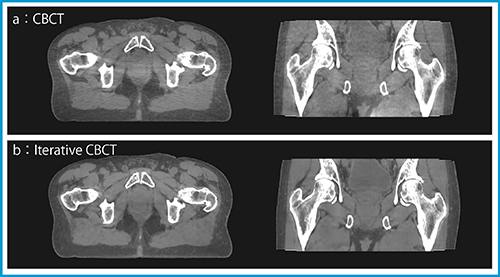

リング形状の新型リニアックであるHalcyon(図1 b)は,TrueBeamと同様に2種類のIGRTシステムを搭載している。「Digital Megavoltage Imager」(DMI)を用いたMVのX線による2D照合もしくはCBCT照合が可能である。また,kV用のkV DMIを用いたCBCT照合も可能となっている。被ばく線量が少なく3D照合が可能なkV CBCTが,基本的に第一選択となる。体幹部領域におけるkV CBCTの撮影時間は最短で16.6秒であり,TrueBeamの約1/4に短縮されている。また,“Iterative CBCT”(i-CBCT)と呼ばれる再構成方式〔Acuros CTS(Computed Tomography Scatter)およびStatistical reconstruction〕を採用しており,軟部組織の画質が大きく向上している(図2)。Halcyonは,必ずCBCTによる照合を行わなければ照射を行うことができないシステムとなっており,IGRTの積算線量はほかのリニアックに比べて高くなる可能性があることに注意しなければならない。また,必然的に治療と同じ回数分のCBCT画像が発生するため,CBCTを利用した線量計算に基づく適応放射線治療(adaptive radiotherapy)4)のルーチン化が実現可能となる。

図2 前立腺治療患者におけるCBCTとi-CBCTの比較

(画像提供:株式会社バリアンメディカルシステムズ)